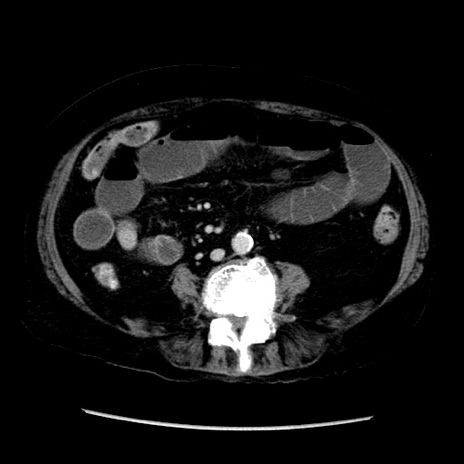

冠状断像

症例14(横断像)

【症例】 90歳代女性

【主訴】 腹痛・嘔吐

【現病歴】今朝から左側腹部痛を認めた。 経過観察していたが、嘔吐を認めたため来院。

【既往歴】 子宮癌術後

【身体所見】 意識清明、BP 127/54mmHg、P 98bpm Sp02 95%(RA)、BT 35.8°C、腹部平坦・軟腸ぜん動音聴取良好、右下腹部圧痛(+) 反跳痛なし

【データ】WBC 9800、CRP 0.46